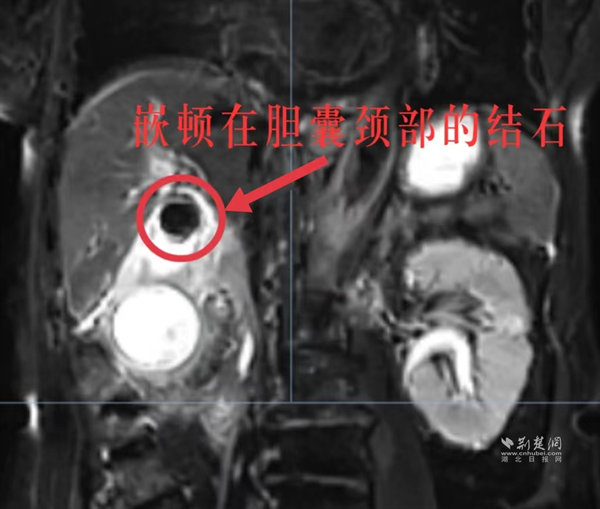

入院后,武汉普仁胡海胆石病医院副主任医师邱实立即为婆婆进行了初步检查,发现其已经出现了腹腔感染。3月26日一早完善的肝胆核磁共振提示,婆婆的胆囊肿成了“大茄子”,胆囊多发结石,胆囊颈部结石嵌顿,胆囊炎,胆囊周围渗出改变。

婆婆嵌顿在胆囊颈部的结石。 通讯员供图

“我们的胆囊出口仅2mm,而付婆婆的结石已经有2cm了,所以结石嵌顿在出口导致胆囊里的胆汁出不去,发生感染、化脓;再加上结石不断摩擦刺激胆囊壁,婆婆的胆囊已经出现坏疽(坏死),如果再拖延下去就会造成胆囊穿孔,到那时胆汁便会流进肚子里导致腹腔大面积感染,最终出现感染性休克,危及生命。”邱实医生解释道。

情况刻不容缓,武汉普仁胡海胆石病医院副院长江帆立即带领胆石病医院专家团队为婆婆的病情进行了详细的评估,在与婆婆本人及家属充分沟通后,江帆院长立即带领专家团队于26日下午为付婆婆行腹腔镜下胆囊切除手术。术中可见,婆婆的胆囊被大网膜及十二指肠致密包裹、粘连严重,胆囊已经肿大到15×7×5cm(正常胆囊约8×5×3cm),有一个茄子大小且呈坏疽样表现;胆囊壁厚达1公分,胆囊颈部一大小约2cm胆色素结石嵌顿。手术全程十分顺利,术后第二天婆婆便能在医生的指导下开始进食、下床活动了。